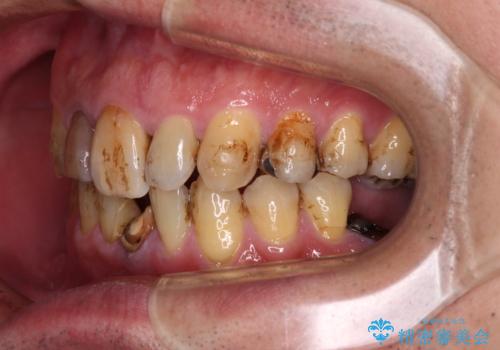

- むし歯治療途中で放置された歯が多く、スペースができたり歯が寄って来たりしているのを気にして来院された患者様です。

矯正治療を行いながら、欠損部はインプラントによる補綴治療を希望されたため、補助装置を用いたワイヤー矯正によりスペースを確保しながら歯列を整え、適宜インプラントを埋入していくこととしました。

上顎前歯もインプラントを希望していらっしゃいましたが、両隣の歯根が近接しており、インプラントは困難と判断したためオールセラミックブリッジによる補綴治療を前提として治療を開始することとしました。

在宅勤務のため、前歯にスペースが長期間できることに対して特に問題はないとおっしゃったため、スペースはそのままに治療を進めていくこととしました。